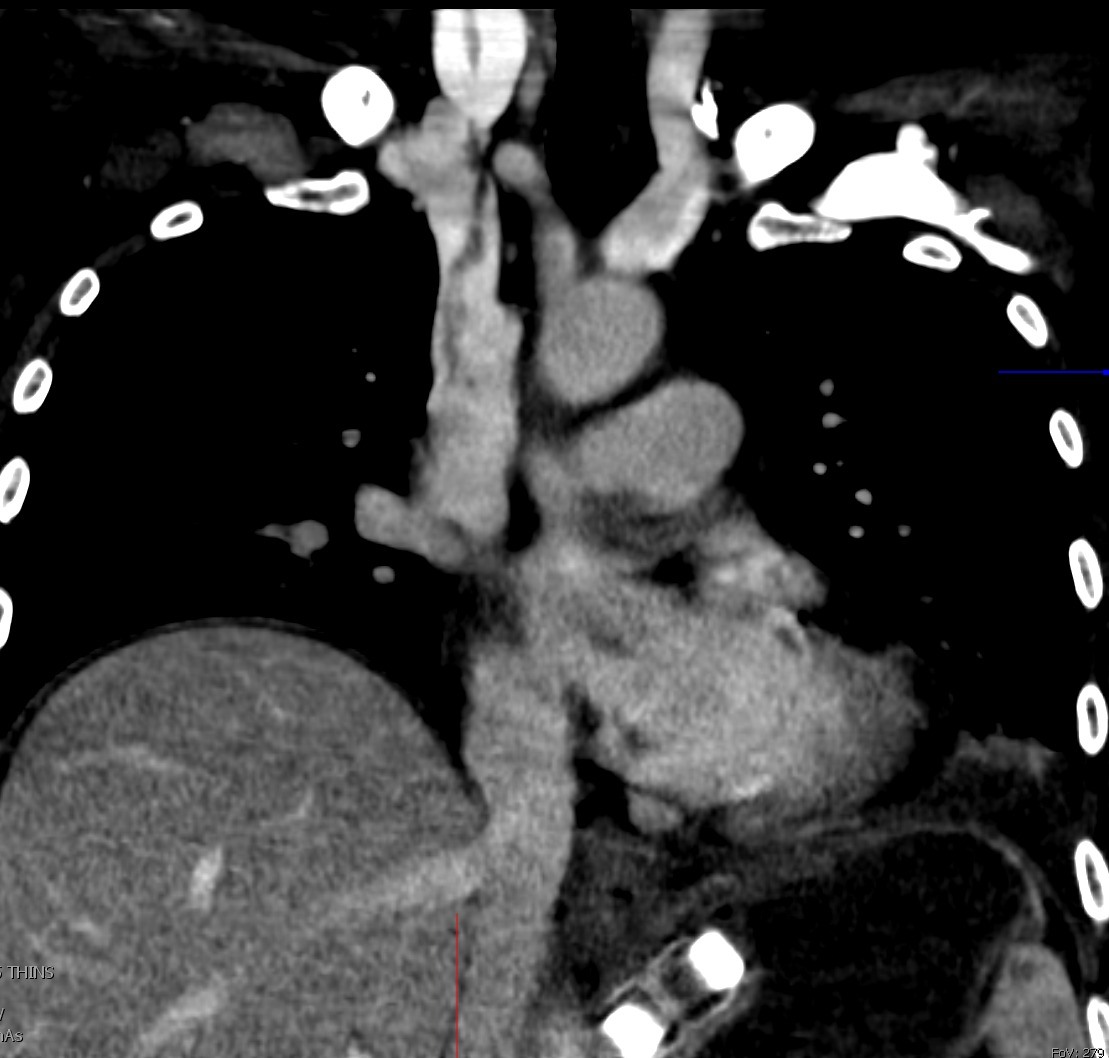

@HsiaoMDPhD

Albert Hsiao θ•­, MD, PhD, FNASCI, FSCMR, FAHA 🐳

1 year

Welcome to July! Time to revisit some classic cardiovascular imaging lessons... what is the key "incidental" finding in this coronal section from a chest CT? #radres @UCSDRadRes @NASCISociety @thoracicrad @ARRS_Radiology @RSNA